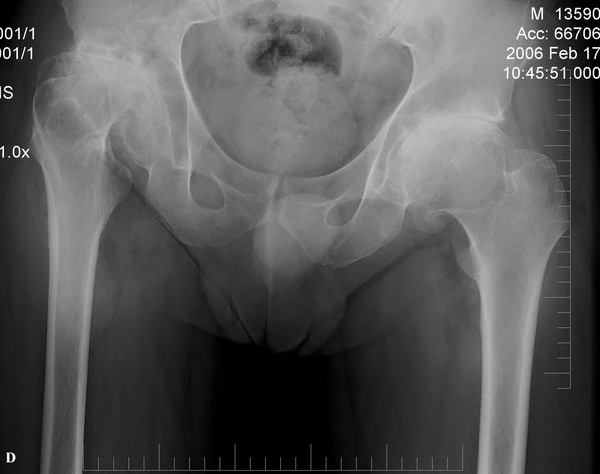

Рентгенография скелета демонстрирует характерные изменения: микроцефалия и платиспондилия — уплощение тел позвонков с характерным центральным вдавлением замыкательных пластинок, создающим эффект «двойного горба». Рёбра при этом заболевании выглядят расширенными. Таз уменьшен в размерах, с узкими костными структурами, при этом подвздошные гребни имеют характерный «кружевной» рисунок за счёт мелких склеротических изменений. Вертлужные впадины деформированы с неровными контурами, лонное сочленение расширено. Головки бедренных костей часто повёрнуты медиально[5].

Осложнения, связанные с скелетными аномалиями, включают компрессию спинного мозга (особенно в шейном отделе из-за нестабильности атлантоаксиального сочленения), подвывихи и вывихи тазобедренных суставов, ограничение подвижности суставов и характерную «утиную» походку[4].